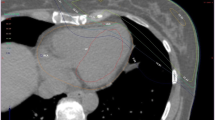

However, it remains to be considered that despite low mean heart doses, relevant areas of the heart can be exposed to doses between 40 and 50 Gy [14], as shown exemplarily in Figs. 1 and 2. Mean heart dose—the only parameter reported in earlier studies—does not seem to reliably reflect the cardiac risk in many cases [15]. Nevertheless, the results of a recently performed practice pattern survey showed that most of the participating radiotherapists consider the mean heart dose to be the most important dose parameter related to heart sparing in breast cancer RT [16].

Three-dimensional (3D) treatment plans with and without gating (transverse slides, dose-wash). Left side: 3D treatment planning without deep-inspiration breathold (DIBH) with normal breathing; right side: the same patient planned using gated breathing with DIBH. Planning target volume (PTV) contoured in red, heart contoured in purple, left ventricle contoured in green, left anterior descending artery (LAD) contoured in yellow

Dose–volume histogram from the two treatment plans shown in Fig. 1. Graphs with triangles: with deep inspiration breathold (DIBH); graphs with squares: without DIBH. Planning target volume (PTV) in red, clinical target volume (CTV) in pink, whole heart in purple, left ventricle in light blue, left anterior descending artery (LAD) in green, left lung in dark blue

The dose values from the treatment planning shown in Fig. 1 and 2 ist showed in detail in Table 1. The aim of the present paper is to critically discuss whether mean heart dose should continue to be regarded as the most relevant parameter for prediction of cardiac toxicities or if dose constraints for substructures of the heart are more relevant. Furthermore, we want to give an overview of techniques to protect the heart and comment on non-radiotherapeutic aspects of cardiotoxicity in the multimodal setting of breast cancer treatment.

In principle, mean heart dose seems to be a valid parameter for predicting cardiac toxicity. It is well-documented that reducing the mean heart dose is associated with lower risks of cardiac late effects [10, 12, 22, 29, 40]. Using modern techniques for breast irradiation, low mean heart does in a range below 2–3 Gy are achievable. Despite such low mean heart doses, subvolumes such as the heart apex or parts of the LAD can be exposed to much higher doses (Figs. 1 and 2; [41]). In a study conducted by the authors using a modern 3D technique with tangential beams to treat left-sided breast cancer, the mean heart dose amounted 2.1 (0.98–8.3) Gy [42]. Nonetheless, maximum doses to small but presumably relevant parts of the anterior part of the LV (“anterior myocardial territory,” AMT; based on Tan et al. [43]) were up to 47.2 Gy. The mean and maximum doses to the LAD were 9.2 (2.1–46.2) Gy and 24.6 (2.8–49.6) Gy, respectively.

The problem is illustrated in Figs. 1 and 2. In Fig. 1, radiation treatment planning scans (transversal planes) of the left breast are shown. In both cases, modern 3D planning was performed. Even without any specific heart-protecting technique, the mean heart dose is below 2.5 Gy. Nevertheless, apical areas like the LAD and LV receive much higher doses.